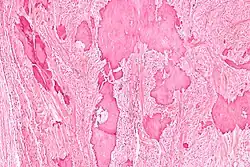

| Low magnification micrograph of a calcified ovarian fibroma in the context of nevoid basal cell carcinoma syndrome. H&E stain. | |

On gross pathology, they are firm and white or tan. On microscopic examination, there are intersecting bundles of spindle cells producing collagen.

There may be thecomatous areas (fibrothecoma). The presence of an ovarian fibroma can cause ovarian torsion in some cases.

Diagnosis is usually made by ultrasonography showing a solid ovarian lesion, or, on some occasions, mixed tumors with solid and cystic components.[1] Computed tomography and magnetic resonance imaging can also be used to diagnose fibromas. In a series of 16 patients, 5 (28%) showed elevated levels of CA-125.[1] Histopathology demonstrates spindle-shaped fibroblastic cells and abundant collagen.[3]